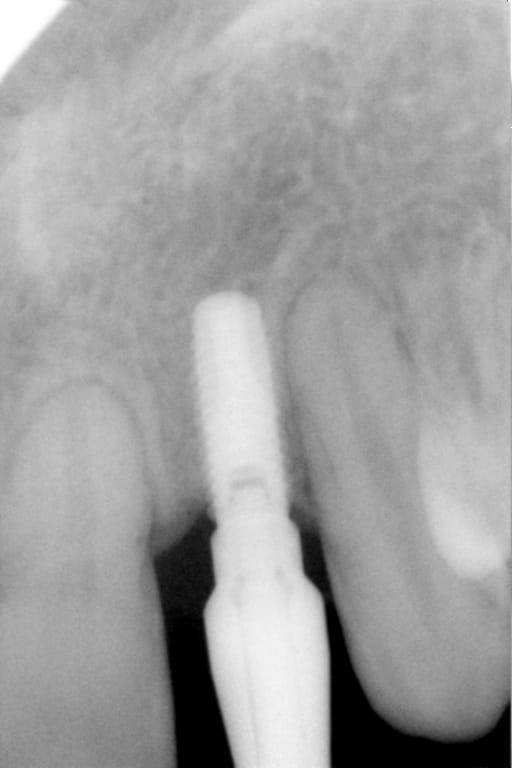

On m'a dit que Pluton était incollable sur les implants.

Alors, j'aimerais demander à Pluton s'il sait ce que c'est...

dis m'en un peu plus sur ce cas car c'est un implant avec un hexagone externe et j'ai beaucoup de correspondances....

cela dit, hex externe en général c'est une plateforme standard et quasi toutes les marques sont compatibles

Alors je n'ai rien de plus. Eventuellement des photos. Et l'année 2003.

donc çà limite un peu les recherches sur les marques disponibles en france à cette époque et la marque d'implant qui match le plus avec les caractéristiques que tu m'as montré (hex externe, apex plat, spires en V, col large, vis de cicat avec hexagone....) c'est un implant Biomet 3i osseotite parallel walled